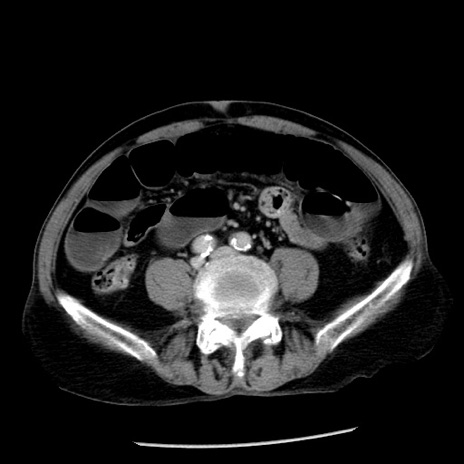

冠状断像

【症例】80歳代男性

【主訴】嘔吐

【現病歴】昨晩2回嘔吐あり、今朝になっても嘔吐あり。来院。

【既往歴】胃潰瘍

【身体所見】意識清明、BT 37.6℃、BP 166/95mmHg、HR 100bpm、SpO2 97%、腹部:平坦・軟、腸蠕動音聴取良好、圧痛なし。

【データ】WBC 21900、CRP 1.46